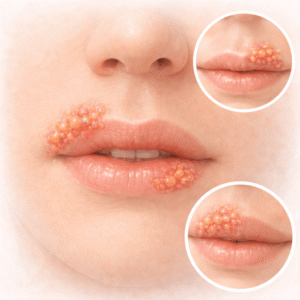

Herpes

Herpese mõistmine Herpes on väga nakkav viirusinfektsioon, mille põhjustab herpes…

Kui kaua kestavad herpese puhangud ja kuidas nendega toime tulla?

Herpese puhangu omamine on nagu oma sõda, mis ei ole alati nähtav,…

Kuidas kiiresti külmetushaavadega Valatsikloviiri abil toime tulla

Herpes huulepõletikud võivad sind tabada kõige ebamugavamal ajal, jättes sind frustreerituks ja…

Valatsikloviir ja külmetushaigused: Mis tõeliselt aitab?

Alusta küsimustikku